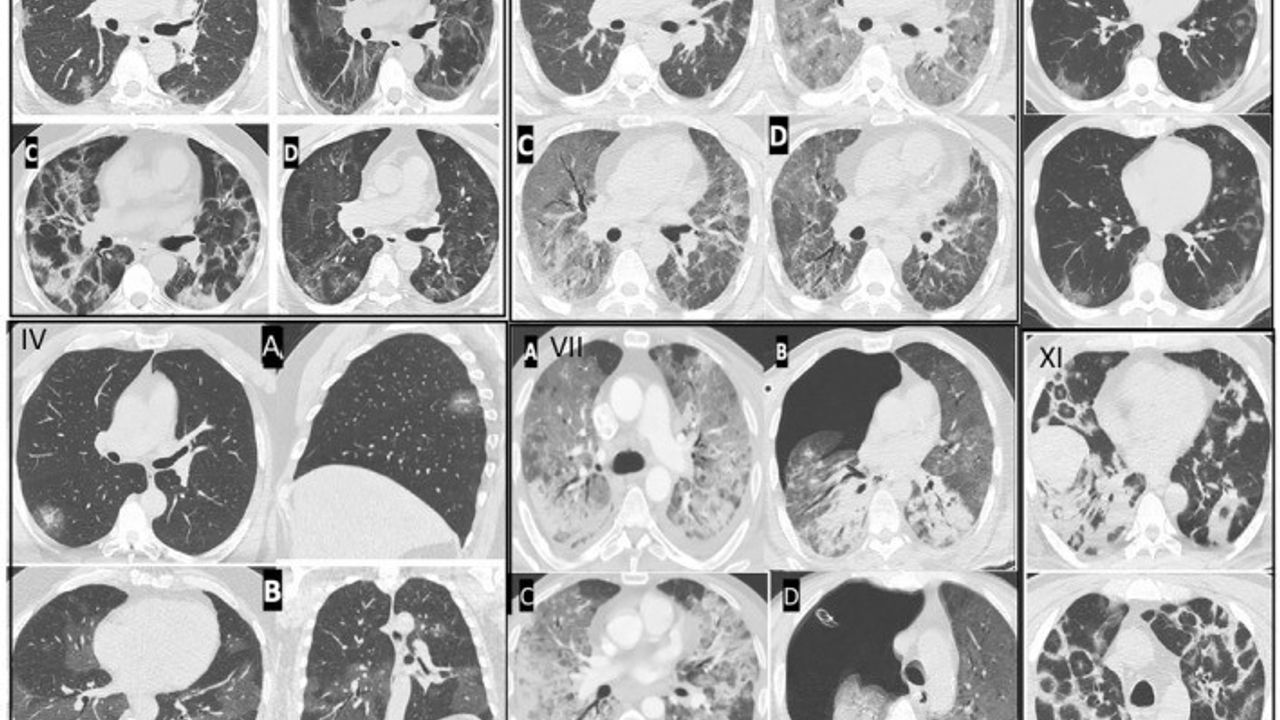

Göğüs Hastalıkları Uzmanı Prof. Dr. Şevket Özkaya, pandemi sonrasında genç yaşta görülen ani ölüm vakalarında artış tespit ettiklerini belirtti. Özkaya, bu artışın nedeninin Kovid-19 virüsünün damarlarda oluşturduğu kalıcı hasar olduğunu vurguladı.

Kılcal damar hasarı ve endotelit

Prof. Dr. Özkaya, pandemi boyunca takip ettikleri binlerce hastada damar iç yüzeyi hasarı yani endotelit saptadıklarını ve bunun ani ölümleri tetiklediğini ifade etti. Özkaya, Avrupa Kalp Dergisi verilerinin de bu durumu "Kovid-19 sonrası damar yaşlanmasının hızlanması" olarak tanımladığını belirtti.

Özkaya, Kovid-19’u geçirenlerde damar yaşının takvim yaşından daha yaşlı hale geldiğini ve bunun bazı kişilerde 5 yıllık yaşlanmaya eşdeğer olduğunu aktardı. Bu değişimin özellikle kılcal damar düzeyinde ciddi işlev bozukluklarına yol açtığını söyledi.

Özkaya'ya göre Kovid-19 geçirmiş ve pandemi öncesi yaptığı ağır sporları aynı şekilde sürdüren gençlerde yoğun egzersiz sırasında ani kalp krizleri görülebiliyor. Bunun nedeni, Kovid-19 sonrası kalp ve akciğer kılcal damarlarındaki hasar yüzünden yeterli oksijenlenmenin sağlanamaması; bu durumun nadiren de olsa ani ölüme kadar varabildiği ifade edildi.